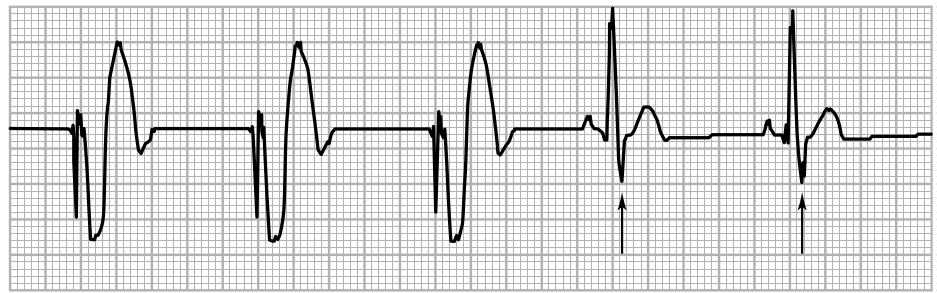

Irregular rhythm

twos.jpg

Irregular rhythm explained

twos_explained.jpg